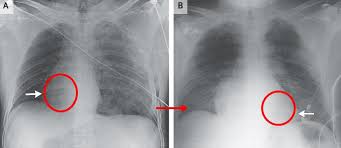

- 심장 위치 이상(dextrocardia): 드물게, 심장이 우측에 위치하는 선천 이상으로, 진단에는 영상검사가 필수입니다 :contentReference[oaicite:19]{index=19}.

- 심장의 위치와 관련해 흉통, 역류음, 전도 이상 등의 진단 시 정확한 해부학적 위치가 큰 도움이 됩니다.